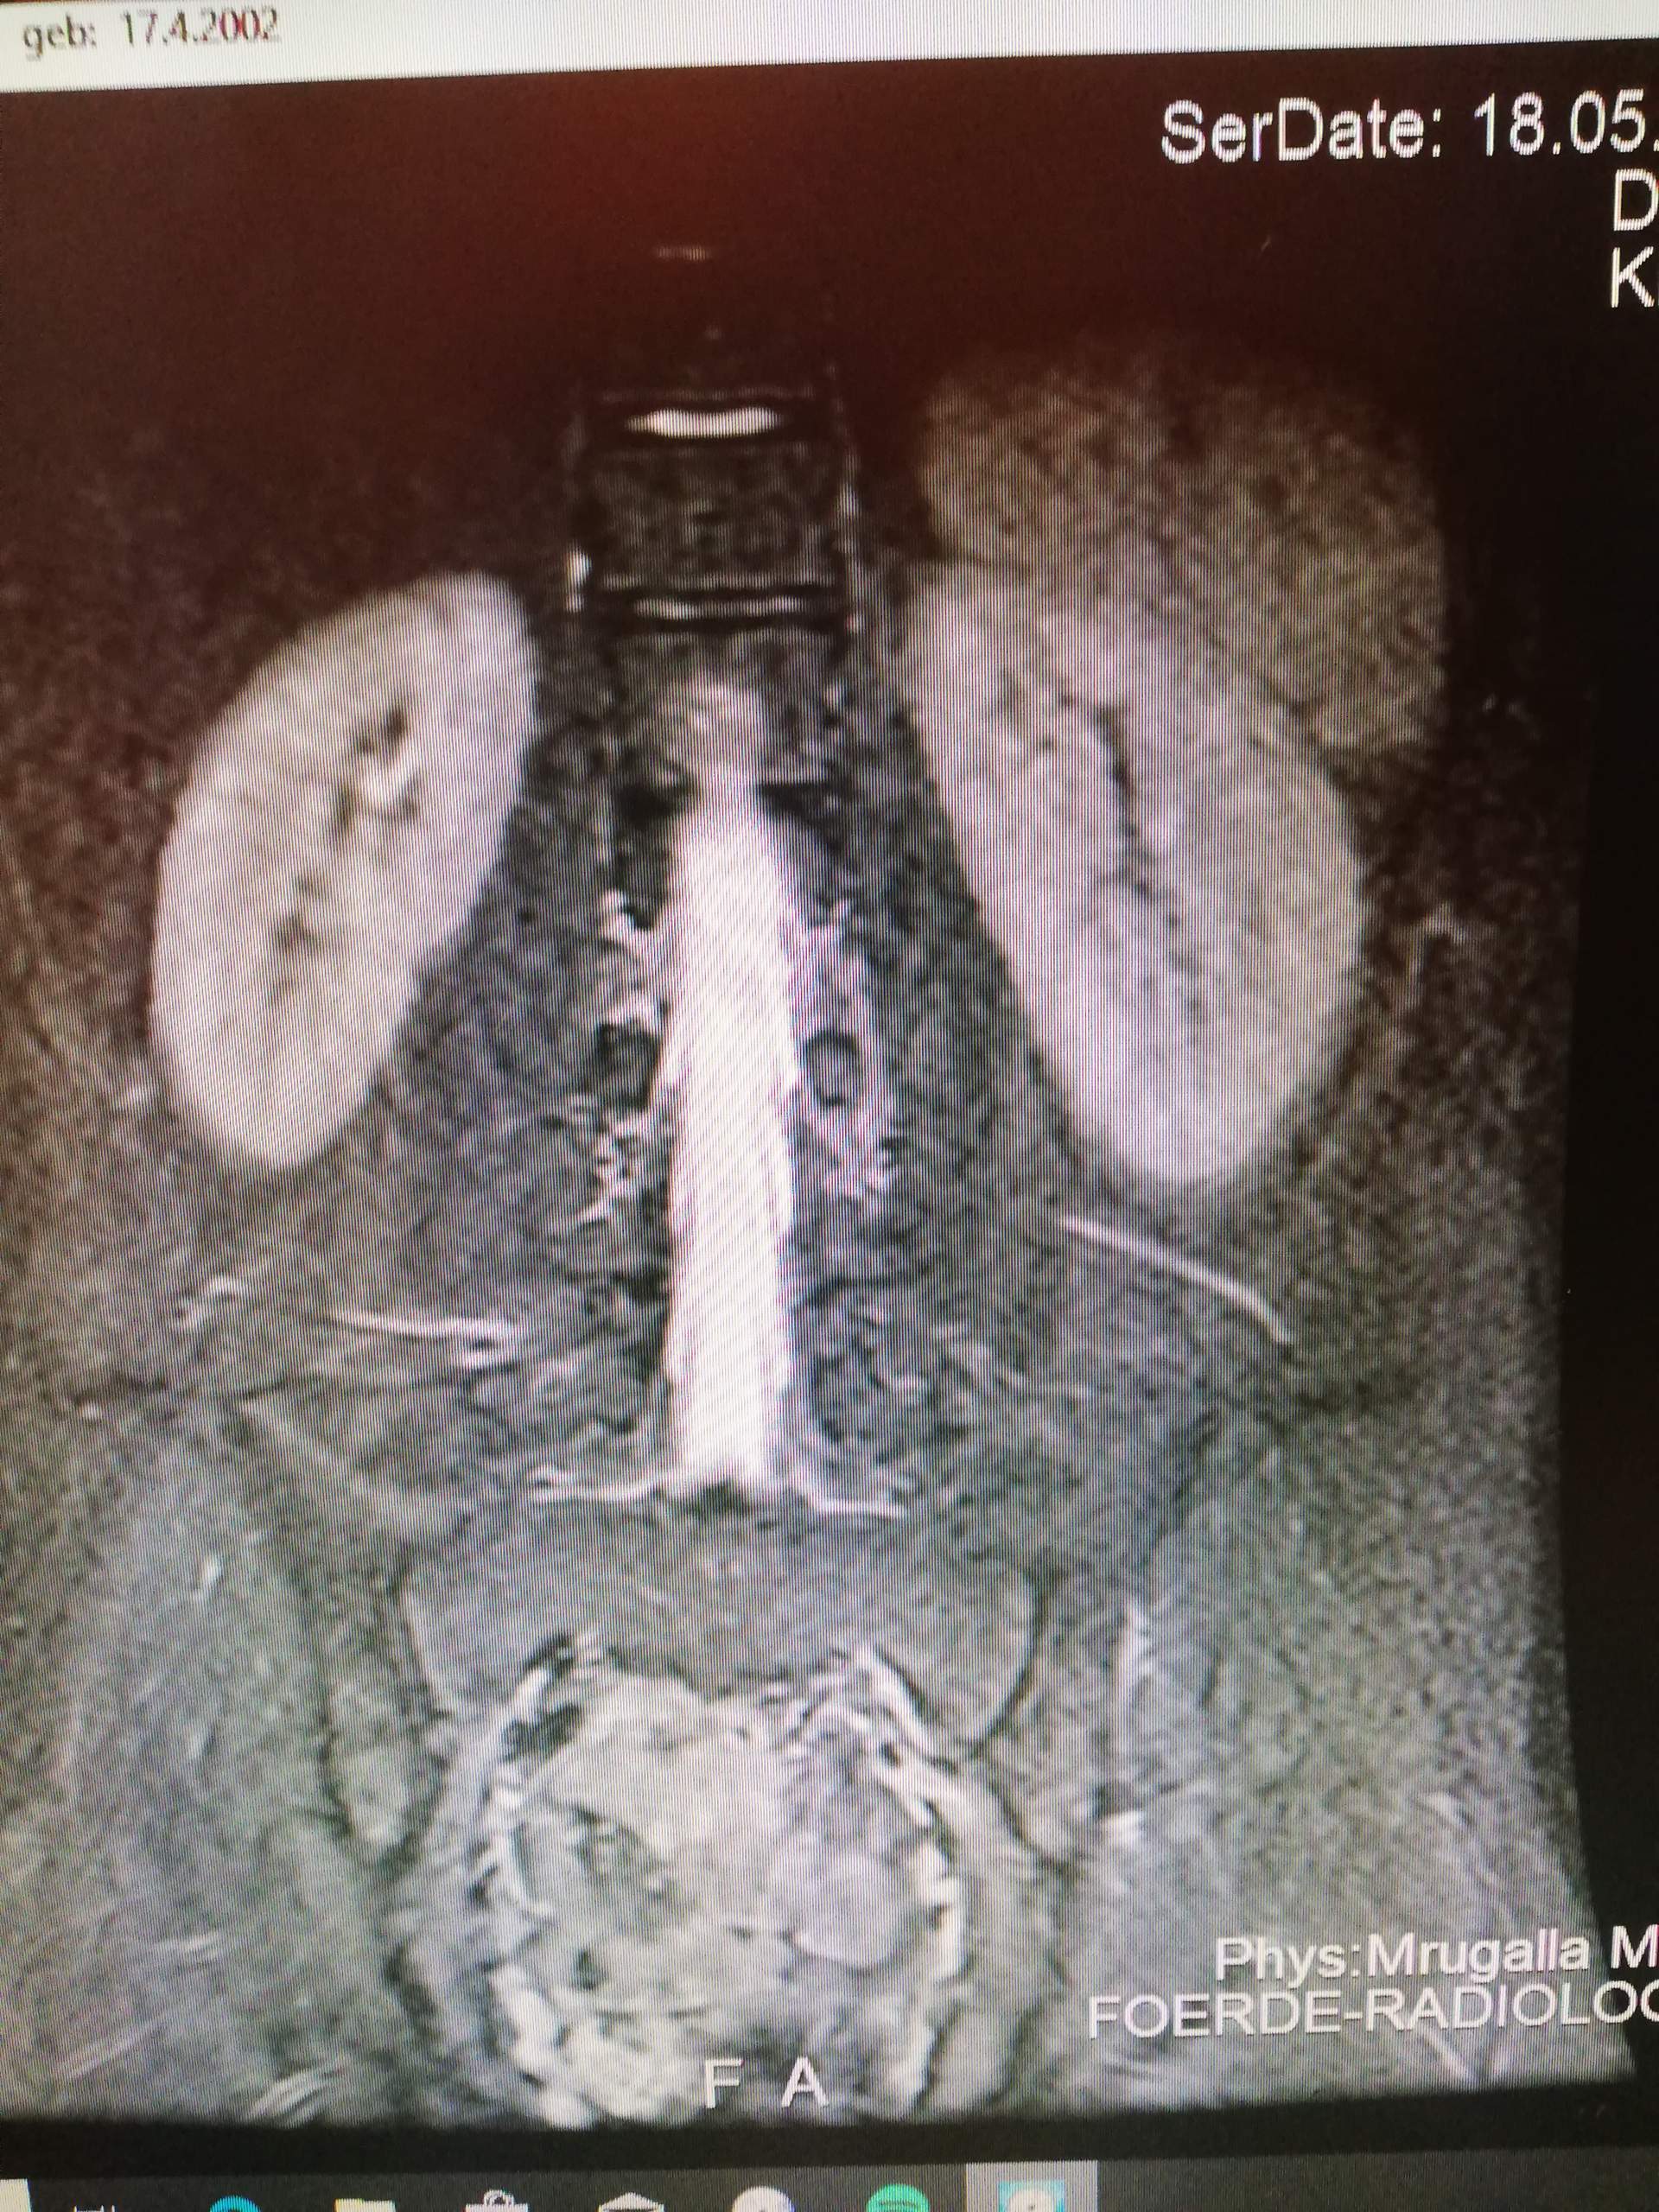

Lumbale radikulopathie. Kann jemand was mit den mrt bildern anfangen von der lws und mir ne

Kann Jemand Was Mit Den MRT Bildern Anfangen Von Der Lws Und Mir Ne

Lumbale radikulopathie: klinik steht vor bildgebung. Kann jemand was mit den mrt bildern anfangen von der lws und mir ne